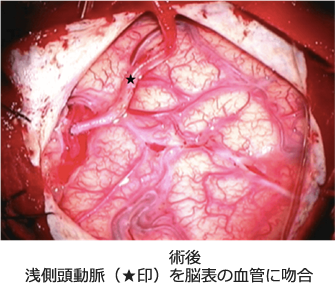

もやもや病の手術方法は、歴史的な変遷を繰り返して様々な手技が個々の施設で行われています。根本的な考え方は、手足の麻痺につながる中大脳動脈領域の血流動態改善が第一目的で、小児ではさらに前頭葉の血流動態改善という目的が加わります。頭皮内を走行している浅側頭動脈を頭蓋内の脳表血管に吻合する直接血行再建術(バイパス手術)と、血管が豊富な側頭筋や硬膜、帽状腱膜などを脳表に移動する間接血行再建術があります。間接血行再建術は、脳表に移動された組織から血管新生がおこり、血液が頭蓋外から脳に流入するという、この疾患特有の現象を利用した方法です。両者の違いは、直接バイパス手術では血流改善効果が吻合直後から得られるのに対して、間接的手術では血管新生までに3週間から1ヶ月という時間的な差です。従って、新生血管形成能が小児ほど確実でないと推測されている成人や、小児でも重症例で血流増加を急ぐ場合には直接バイパス手術が必要です。前頭葉に対して、浅側頭動脈の前頭枝を用いて2つ目の直接血管吻合を行う方法もありますが、知能予後の考慮という目的からは、血流改善に即効性は求めないと考えて、当科では前頭葉に対しては間接的手術を行い、手術時間を短縮して手術侵襲を低くしています。